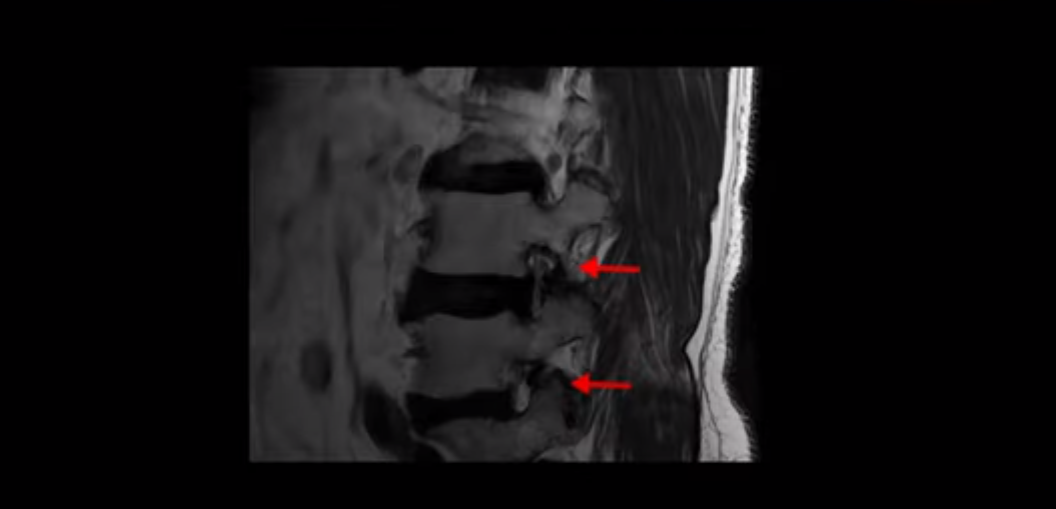

이 환자분은 고관절 쪽이 10년이 넘게 아팠고, 5년 전에는 갑자기 허벅지와 다리가 아파 못 걷게 돼서 허리 수술을 받습니다. 그리고 3년 후에 다시 재발합니다. 고관절 통증은 허리 수술 이후에도 좋아지지 않고 계속 아팠습니다. 수술하고 재발한 이후로 원래부터 아프던 고관절은 물론, 양쪽 엉덩이와 사타구니 및 허벅지가 다 아파서 잘 걷지도 못하고 또 앉거나 누워도 아파서 뒤척거리기도 힘듭니다. 이분 MRI를 보면 여러 마디가 다 안 좋습니다.

4번 5번에는 왼쪽으로 이전에 수술한 자국이 보이는데

수술한 부위에 상처 조직이 생겨 유착된 부위가 보입니다. 왼쪽, 오른쪽 신경 가지가 빠져나가는 추간공을 보면 오른쪽도 여러 마디가 좁아져 있고

왼쪽도 여러 마디가 좁아져 있습니다.

이렇게 허리 여러 마디와 신경 나가는 구멍 오른쪽, 왼쪽이 다 안 좋으니까 양쪽 엉덩이와 다리가 다 아픈 겁니다.